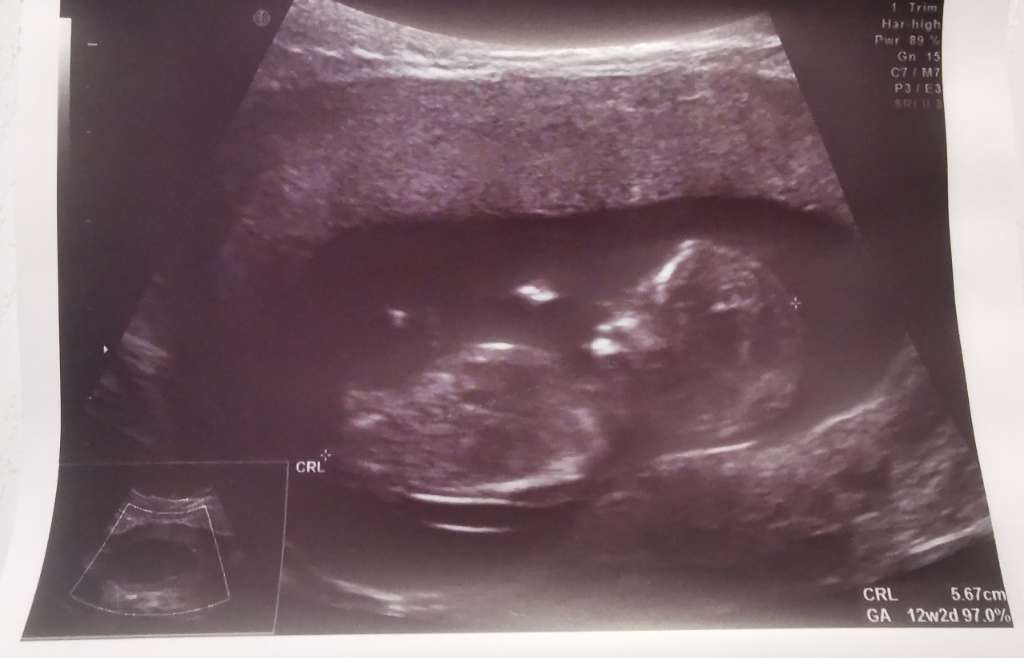

Cześć dziewczyny, może któraś z was zobaczy coś tam? Dodałam już też na ramzi i nub, ale oczekuje na zatwierdzenie 🥰

• 6cb87bc8-17c4-4f8a-b2fd-9816ce43d94f.jpeg

6cb87bc8-17c4-4f8a-b2fd-9816ce43d94f.jpeg

33,4 KB · Wyświetleń: 478

Według mnie dziewczynka, ale lekarzem nie jestem 😅 chyba widać tam wyrostek płciowy. I jeżeli to faktycznie to to wygląda na wyrostek płciowy zwiastujący dziewczynkę. Ale tak jak mówie TO MOJE ZDANIE TYLKO :) potwierdzenie da Cię lekarz.